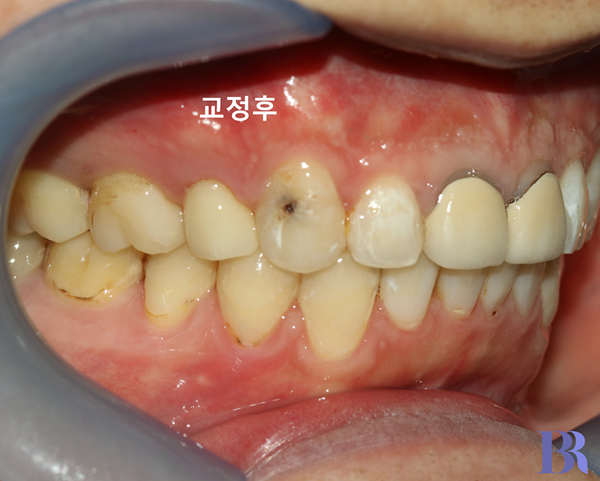

교정 후 입안 우측 모습

윗니와 아랫니 차이가

많이 줄어들었습니다.

교합도 어금니가 직립되면서

긴밀해진 것을 알 수 있습니다.

양치질이 잘 안되는 환자분이라

충치가 아쉽긴 하네요.